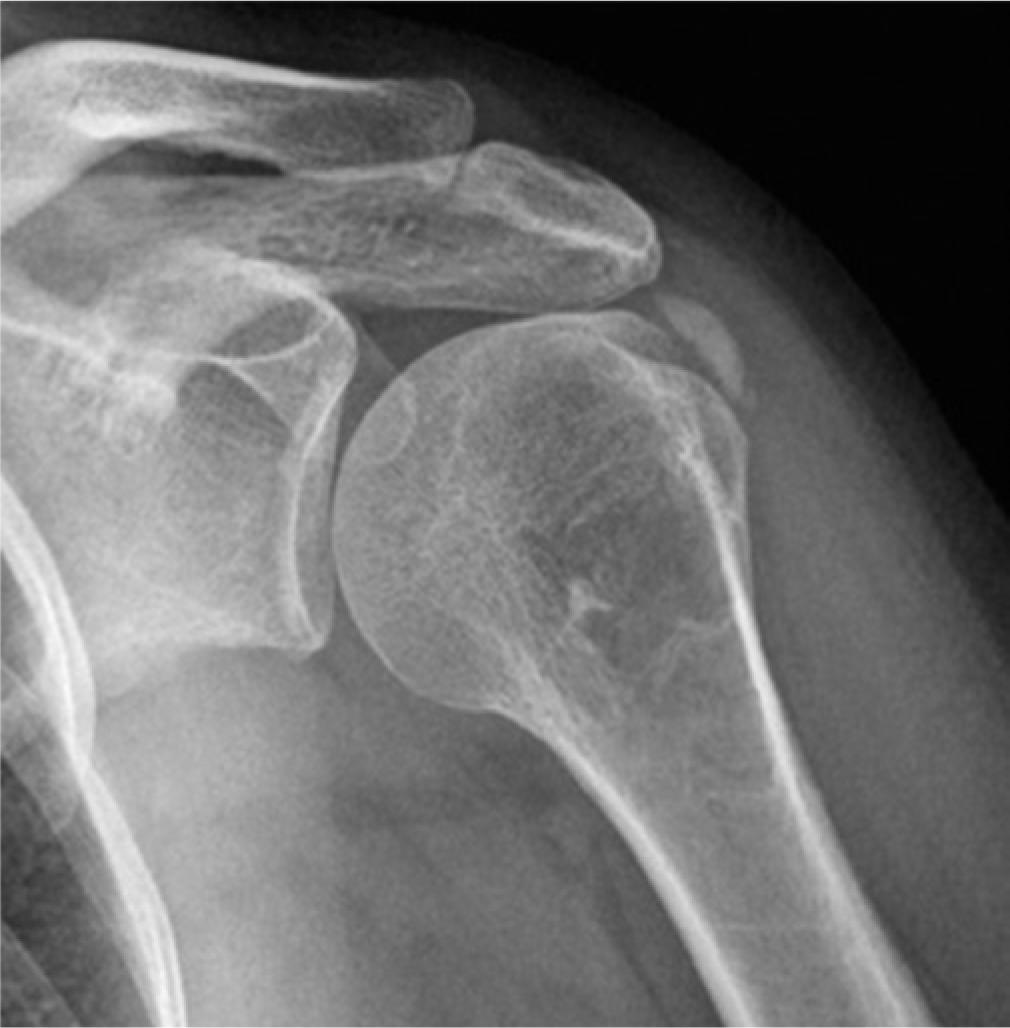

Night pain can be caused by subdeltoid subacromial bursitis, osteoarthritis, glenohumeral joint capsulitis and a bone tumor. In these patients, it may also be prudent to take a plain radiograph to assess the bone and joint.

If the loss of external rotation feels like a bony block, then there may be significant glenohumeral joint osteoarthritis rather than a capsulitis. Not all patients sent for an ultrasound examination have had a prior X-ray to exclude this diagnosis.

In the acute phase, the calcification can be very cloudy and sometimes difficult to see with ultrasound. It will not cause significant acoustic shadowing and will be particularly hard to identify if using compound imaging on the ultrasound machine. To make the calcification more conspicuous, the operator should switch off the compounding technology. The calcification may be easier to identify with a conventional radiograph at this early stage (Fig. 4 and Fig. 5).

Calcific tendinosis seen in Figure 4 on X-ray